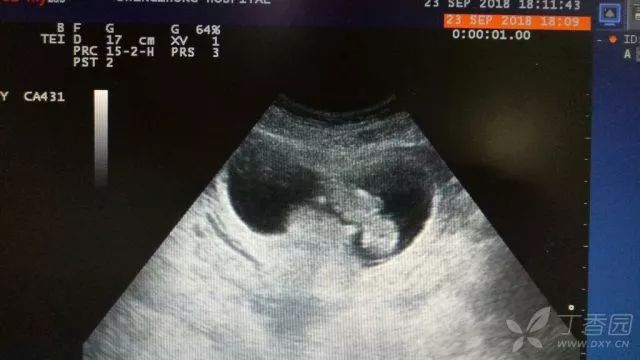

终于,在超声下,我看到了搏动的小心脏——

图片由作者提供

女孩先是直呼不可能,但在事实面前,她不得不承认,「有过性生活,但有避孕措施。」